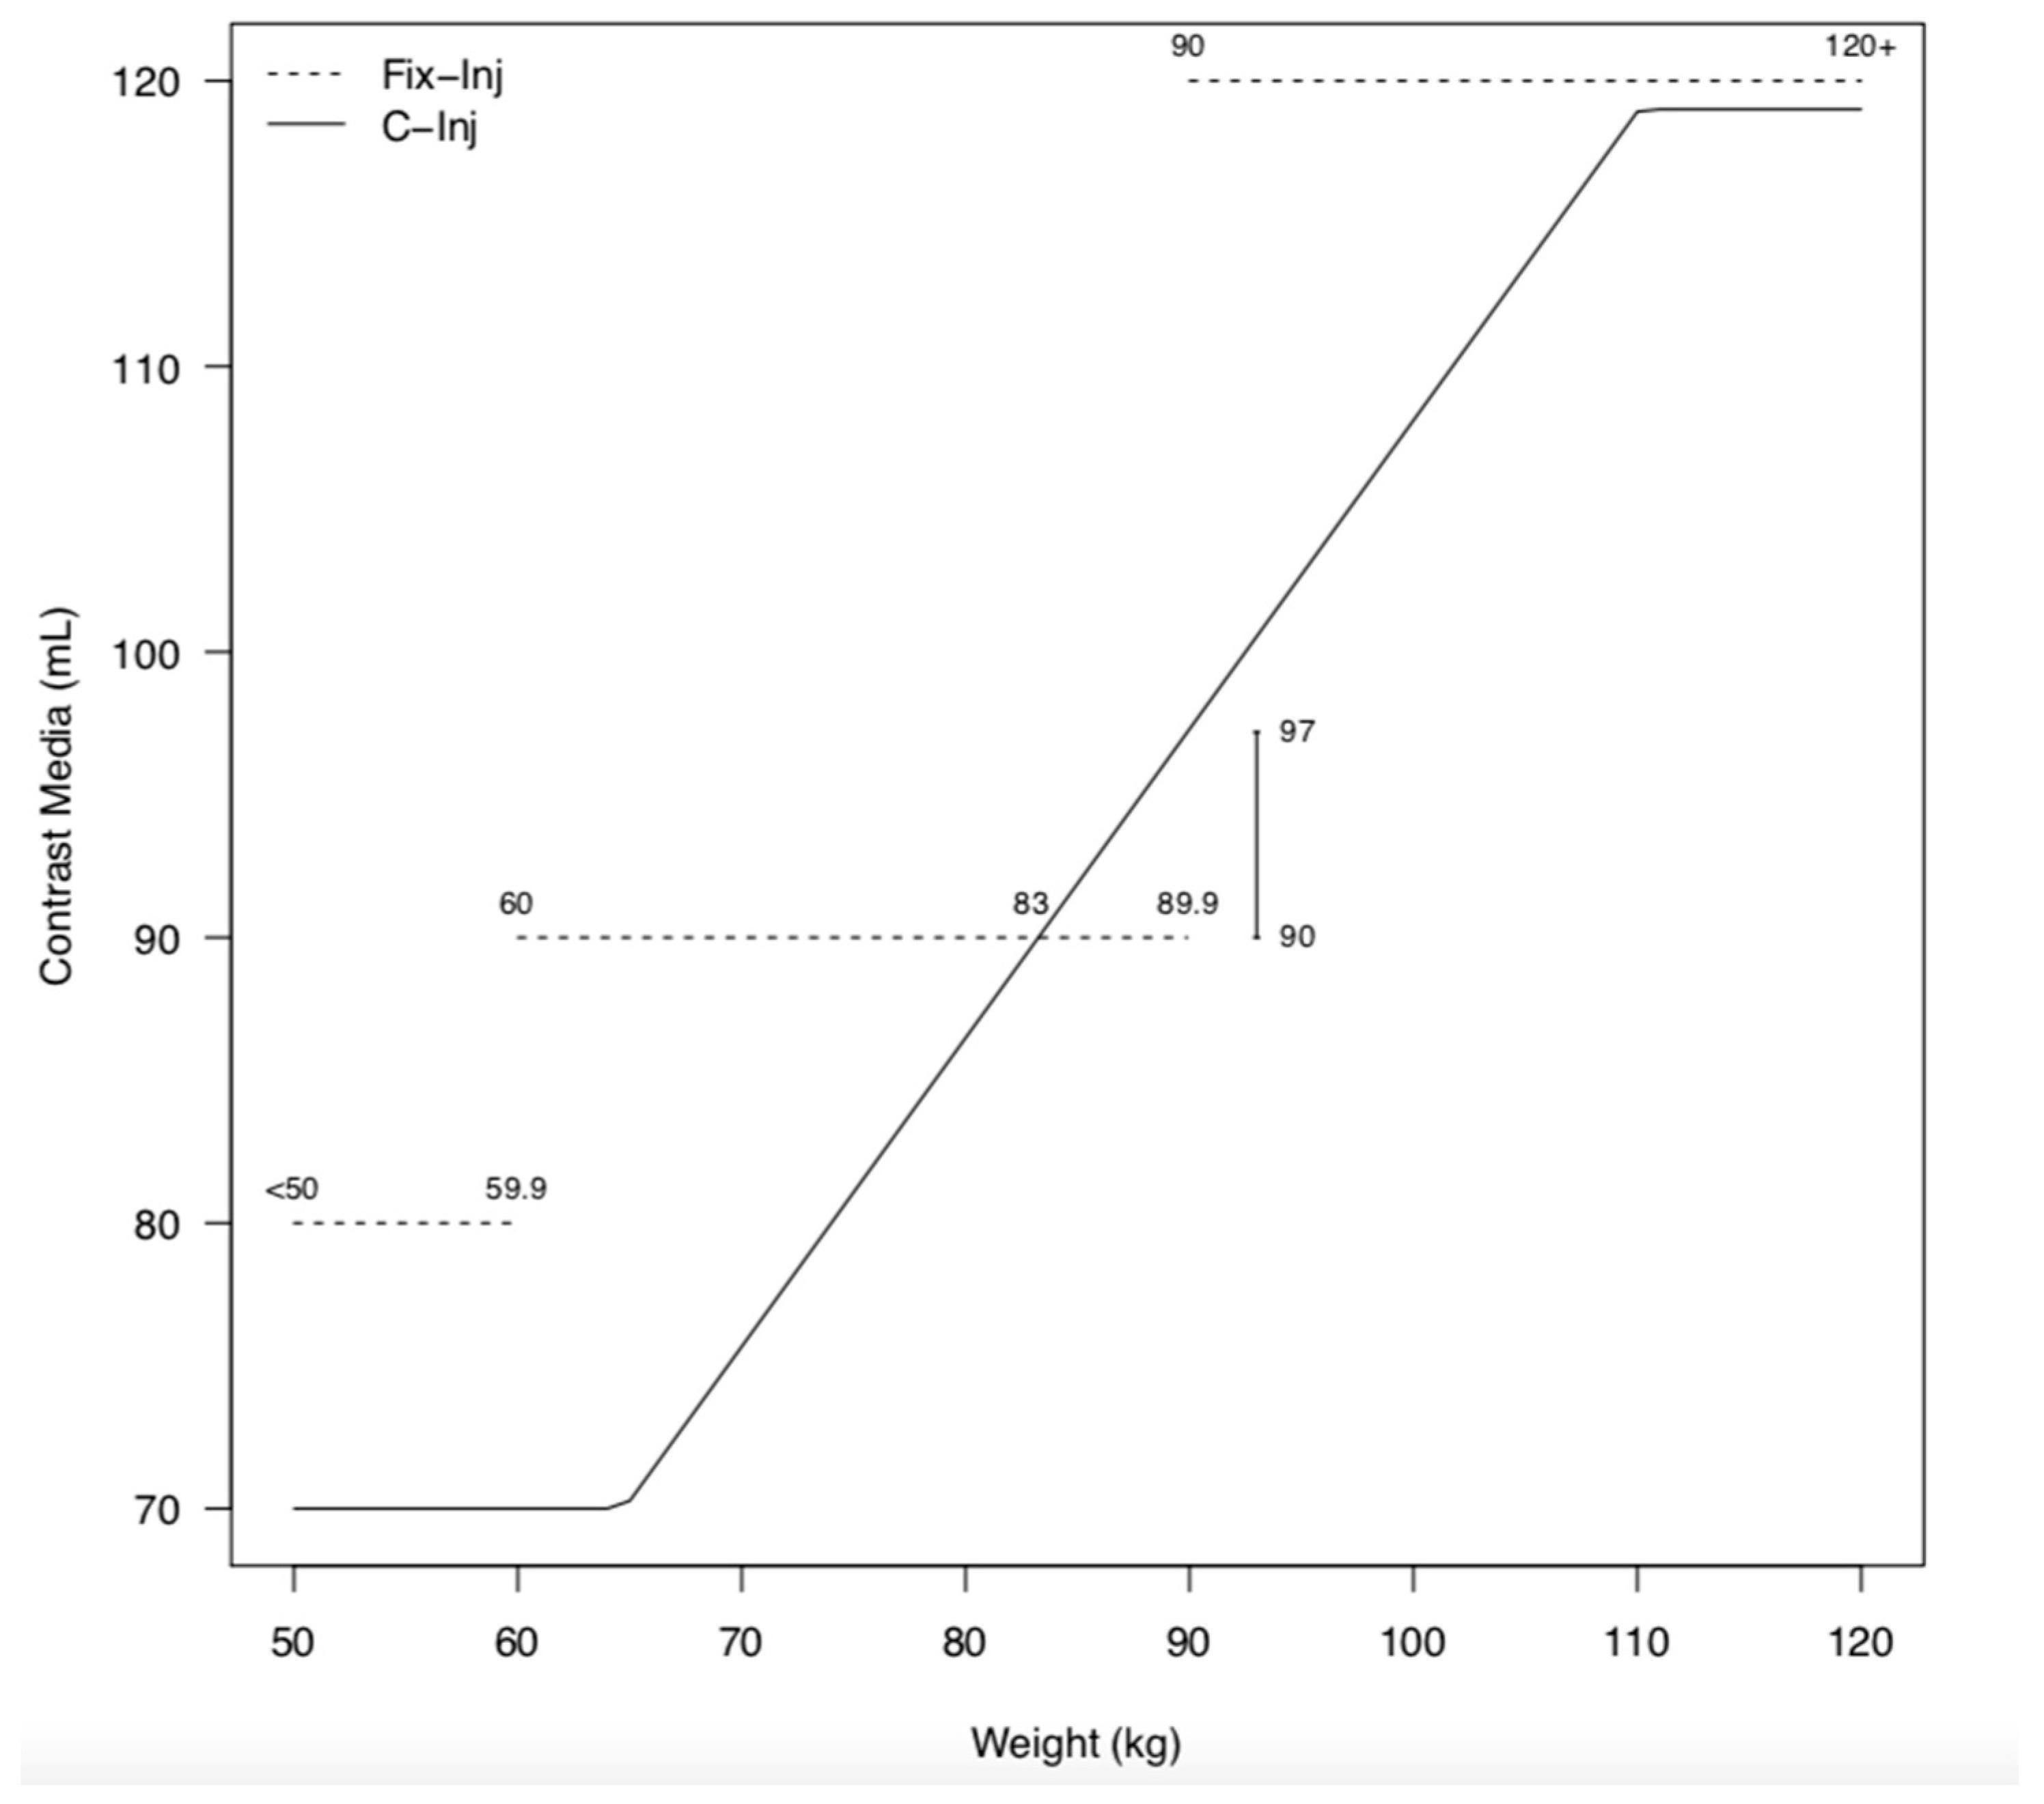

2.3. Contrast Media Protocol

3.2. Contrast Media Injections